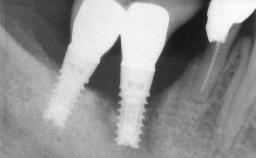

Le Fort I Interpositional Graft and Mandibular Sandwich Osteotomy for Maxillofacial Rehabilitation after Severe Periodontitis

A 47-year-old woman who had suffered from aggressive periodontitis requiring a number of periodontal interventions over more than 10 years was referred by her general dental practitioner and periodontologist for bone augmentation and implant therapy. Her failing dentition had already been scheduled for extraction. The patient expressed a desire for implant-supported fixed restorations and esthetic improvement of her lower face. She had agreed to consult with a maxillofacial surgeon after the referring dentist had suggested bone augmentation. An initial examination by the maxillofacial surgeon revealed mobility of all residual teeth in a patient who was very unhappy with the function of her removable partial dentures. Due to periodontally migrated flaring teeth and loss of occlusal support, the vertical dimension of occlusion was dramatically reduced. The patient was displeased with her lower face because of deepened nasolabial, commissural, and supramental folds.

# of Implants 14

Bone Augmentation Horizontal|Sinus Floor Elevation|Staged|Vertical

Bone Volume Deficient vertically or deficient vertically AND horizontally